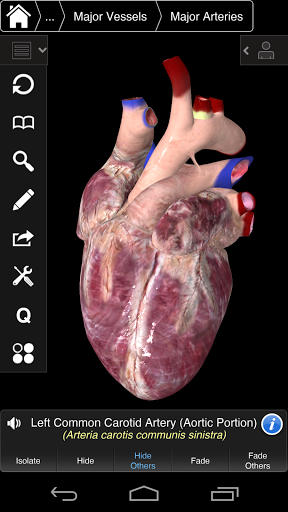

Zawiera także mózg i serce

---- Nowa technologia 3D za pomocą najnowszego silnika graficznego 3D4Medical

---- Ponad 4000 bardzo szczegółowych struktur anatomicznych

---- Tryb wielokrotnego wyboru - Ukryj / Zniknij / Izoluj pojedyncze lub wiele struktur

---- Prawidłowa wymowa audio dla każdej struktury

---- nomenklatura łacińska dla każdej struktury anatomicznej